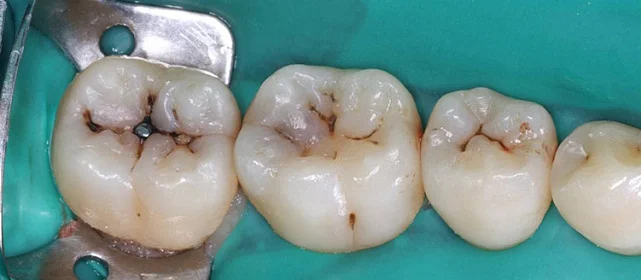

Проблема: В клинику обратился мужчина с жалобами на неправильное положение зубов и смыкание — ряды сходились некорректно, зубы стояли со смещением. При этом было важно, чтобы лечение оставалось незаметным для окружающих, поэтому вариант с брекетами не рассматривался.

Нарушение соотношения челюстей и неправильное положение зубов — зубные ряды смыкались некорректно, зубы стояли со смещением.